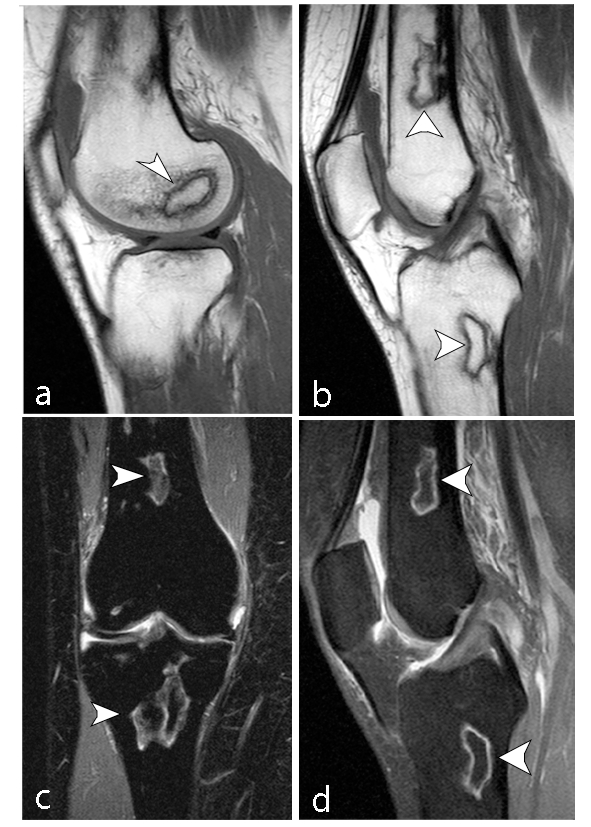

La ON de la cabeza humeral conocida como enfermedad de Hass es la segunda en frecuencia, se desarrolla en la región subcondral, puede provocar colapso del hueso subcondral necrótico, desarrollo de una superficie articular irregular y posterior degeneración de la articulación.

Puede tener varias etiologías: idiopática, secundaria a causas médicas (por fijación quirúrgica o artroscopia), farmacológica o secundaria a un trauma, siendo ésta última la más frecuente. Las fracturas de la cabeza humeral con tres fragmentos pueden desarrollar ON en 3 a 14% de incidencia, mientras que aquellas con cuatro fragmentos, entre 13 y 34%.19

Existe una escala para determinar el grado de severidad de la necrosis mediante hallazgos imagenológicos por RM con el fin de identificar y guiar el tratamiento adecuado, siendo esta la clasificación de Cruess Modificado (►Tabla 4) a partir de la clasificación Ficat y Arlet (►Figs. 9 y 10).20

Hertel describe criterios radiográficos como predictores de isquemia para establecer el compromiso vascular de la cabeza humeral: extensión metafisaria de la cabeza humeral de < 8mm y la disrupción del eje medial > 2mm. Estos hallazgos, en asociación a una fractura del cuello anatómico, presentaron un valor positivo predictivo de 97% para el desarrollo de isquemia.19